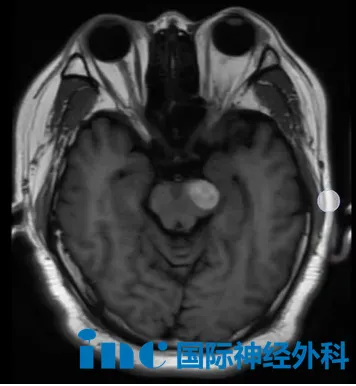

44岁的唐先生就是其中之一。2025年6月,他因右手无力就诊,意外查出脑干海绵状血管瘤,大小约1.7厘米乘1.3厘米。当时医生评估后认为手术风险较高,建议先观察保守治疗。今年4月复查时,影像学检查发现中脑左侧异常信号,结合病史考虑为海绵状血管瘤,且可能伴有再次出血,唐先生右侧肢体无力的症状也确实出现了加重。

关于手术时机,巴教授建议他不要继续拖延。教授同时提到了另一位患者的情况:同样被建议尽快手术,但在咨询后不到一个月时间内病情突然加重,短时间内肿瘤体积增大并再次出血,症状从最初的轻微麻木头晕发展至四肢无力和言语不清。